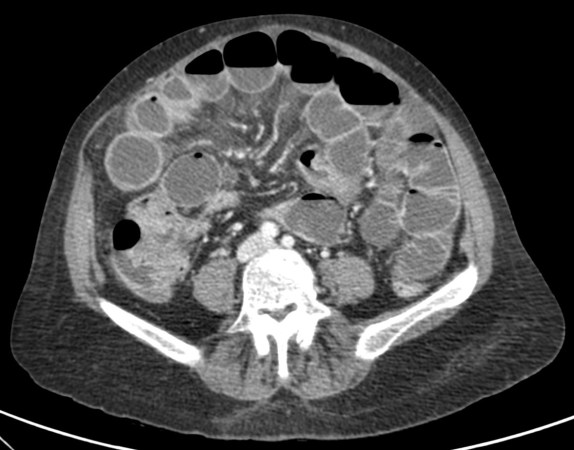

Se realiza TC de abdomen en vacío y con contraste en fase portal:

Estamos ante un cuadro de isquemia intestinal en un paciente con bajo gasto cardiaco con afectación principal de asas intestino delgado, territorio vacularizado por la arteria mesentérica superior.